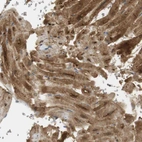

Immunohistochemical staining of human heart muscle shows moderate cytoplasmic positivity in cardiomyocytes.